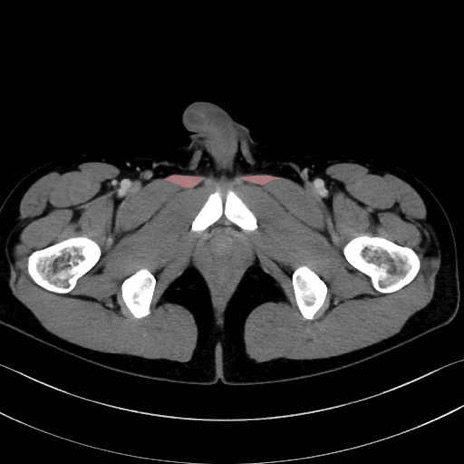

長内転筋(Adductor longus muscle)のCT画像の解剖

長内転筋 (Adductor longus)